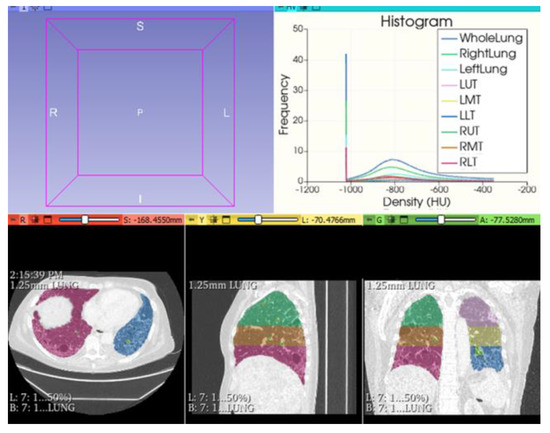

- Fedorov, A.; Beichel, R.; Kalpathy-Cramer, J.; Finet, J.; Fillion-Robin, J.-C.; Pujol, S.; Bauer, C.; Jennings, D.; Fennessy, F.M.; Sonka, M.; et al. 3D Slicer as an Image Computing Platform for the Quantitative Imaging Network. Magn. Reson. Imaging 2012, 30, 1323–1341. [Google Scholar] [CrossRef]

- Maldonado, F.; Moua, T.; Rajagopalan, S.; Karwoski, R.A.; Raghunath, S.; Decker, P.A.; Hartman, T.E.; Bartholmai, B.; Robb, R.A.; Ryu, J. Automated quantification of radiological patterns predicts survival in idiopathic pulmonary fibrosis. Eur. Respir. J. 2014, 43, 204–212. [Google Scholar] [CrossRef]

- Romei, C.; Tavanti, L.M.; Taliani, A.; De Liperi, A.; Karwoski, R.; Celi, A.; Palla, A.; Bartholmai, B.J.; Falaschi, F. Automated Computed Tomography analysis in the assessment of Idiopathic Pulmonary Fibrosis severity and progression. Eur. J. Radiol. 2020, 124, 108852. [Google Scholar] [CrossRef]